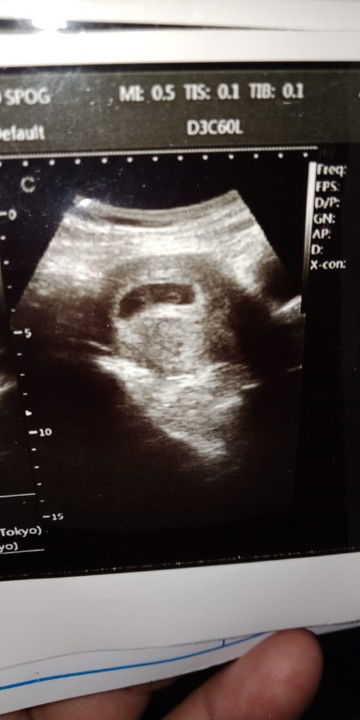

usg 7 mggu

Ini hasil usg waktu 7w+-12d bun ... Tpi itungan br 5 mggu,, Waktu itu kta dokter janin belum terlihat,,, ato blul berkembng ,,,lupa,,, Dn wktu liat dimonitor emng gk terlihat sih.. Tp as udh diprint..diliat dirumah trnyata ada titik nya... Adakah bunda yg punya pengalaman sya... Sya gagal pham dg hasil usg ini...mnrut bunda gimna bun,,,